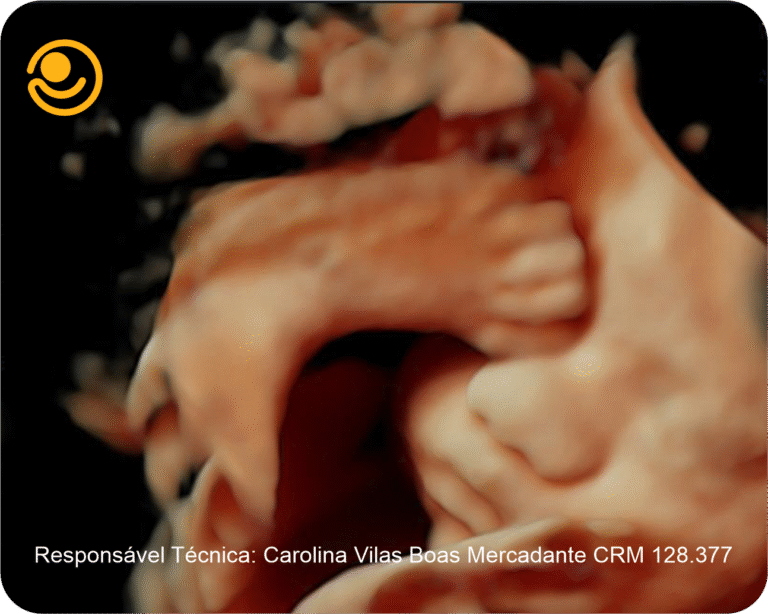

Imagens 3D / 4D

✓ Ultrassonografia 3D/ 4D com imagem em HD